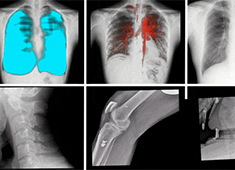

哪些因素會影響DR圖像質量呢?普愛醫療歸納了以下幾大因素。當前國產DR都尤其重視圖像后處理系統的升級,如普愛醫療研發生產的多功能動態DR(型號:PLX8100),應用了公司自主研發的組織均衡技術,它是基于低灰度區擴展到高...

百微米DR的臨床優勢:呈現更豐富的成像細節

目前市面上已經開始漸漸流行“百微米DR”,百微米DR好在哪里,具有什么樣的臨床優勢?以PERLOVE品牌的PLX8100為例,這是一款大尺寸的多功能動態DR機,搭載了高性能的百微米平板,4K*4K采集矩陣與100μm像素...